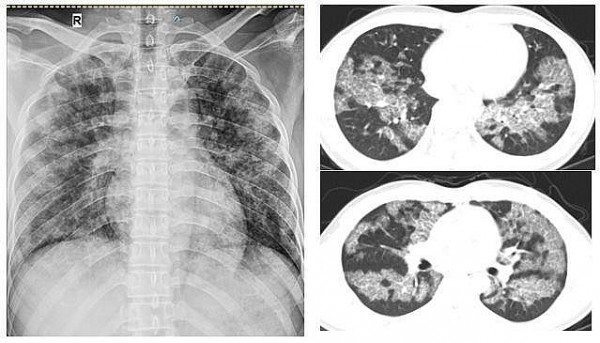

Bệnh viên đa khoa tỉnh Phú Thọ: Điều trị ca bệnh tích tụ protein phế nang hiếm gặp bằng phương pháp rửa phổi

SKV - Người bệnh 31 tuổi mắc bệnh lý hiếm gặp gây khó thở, tức ngực khi gắng sức, tổn thương lan tỏa hai bên phổi, đã được các bác sĩ tại Bệnh viện đa khoa tỉnh Phú Thọ tiến hành rửa phổi.